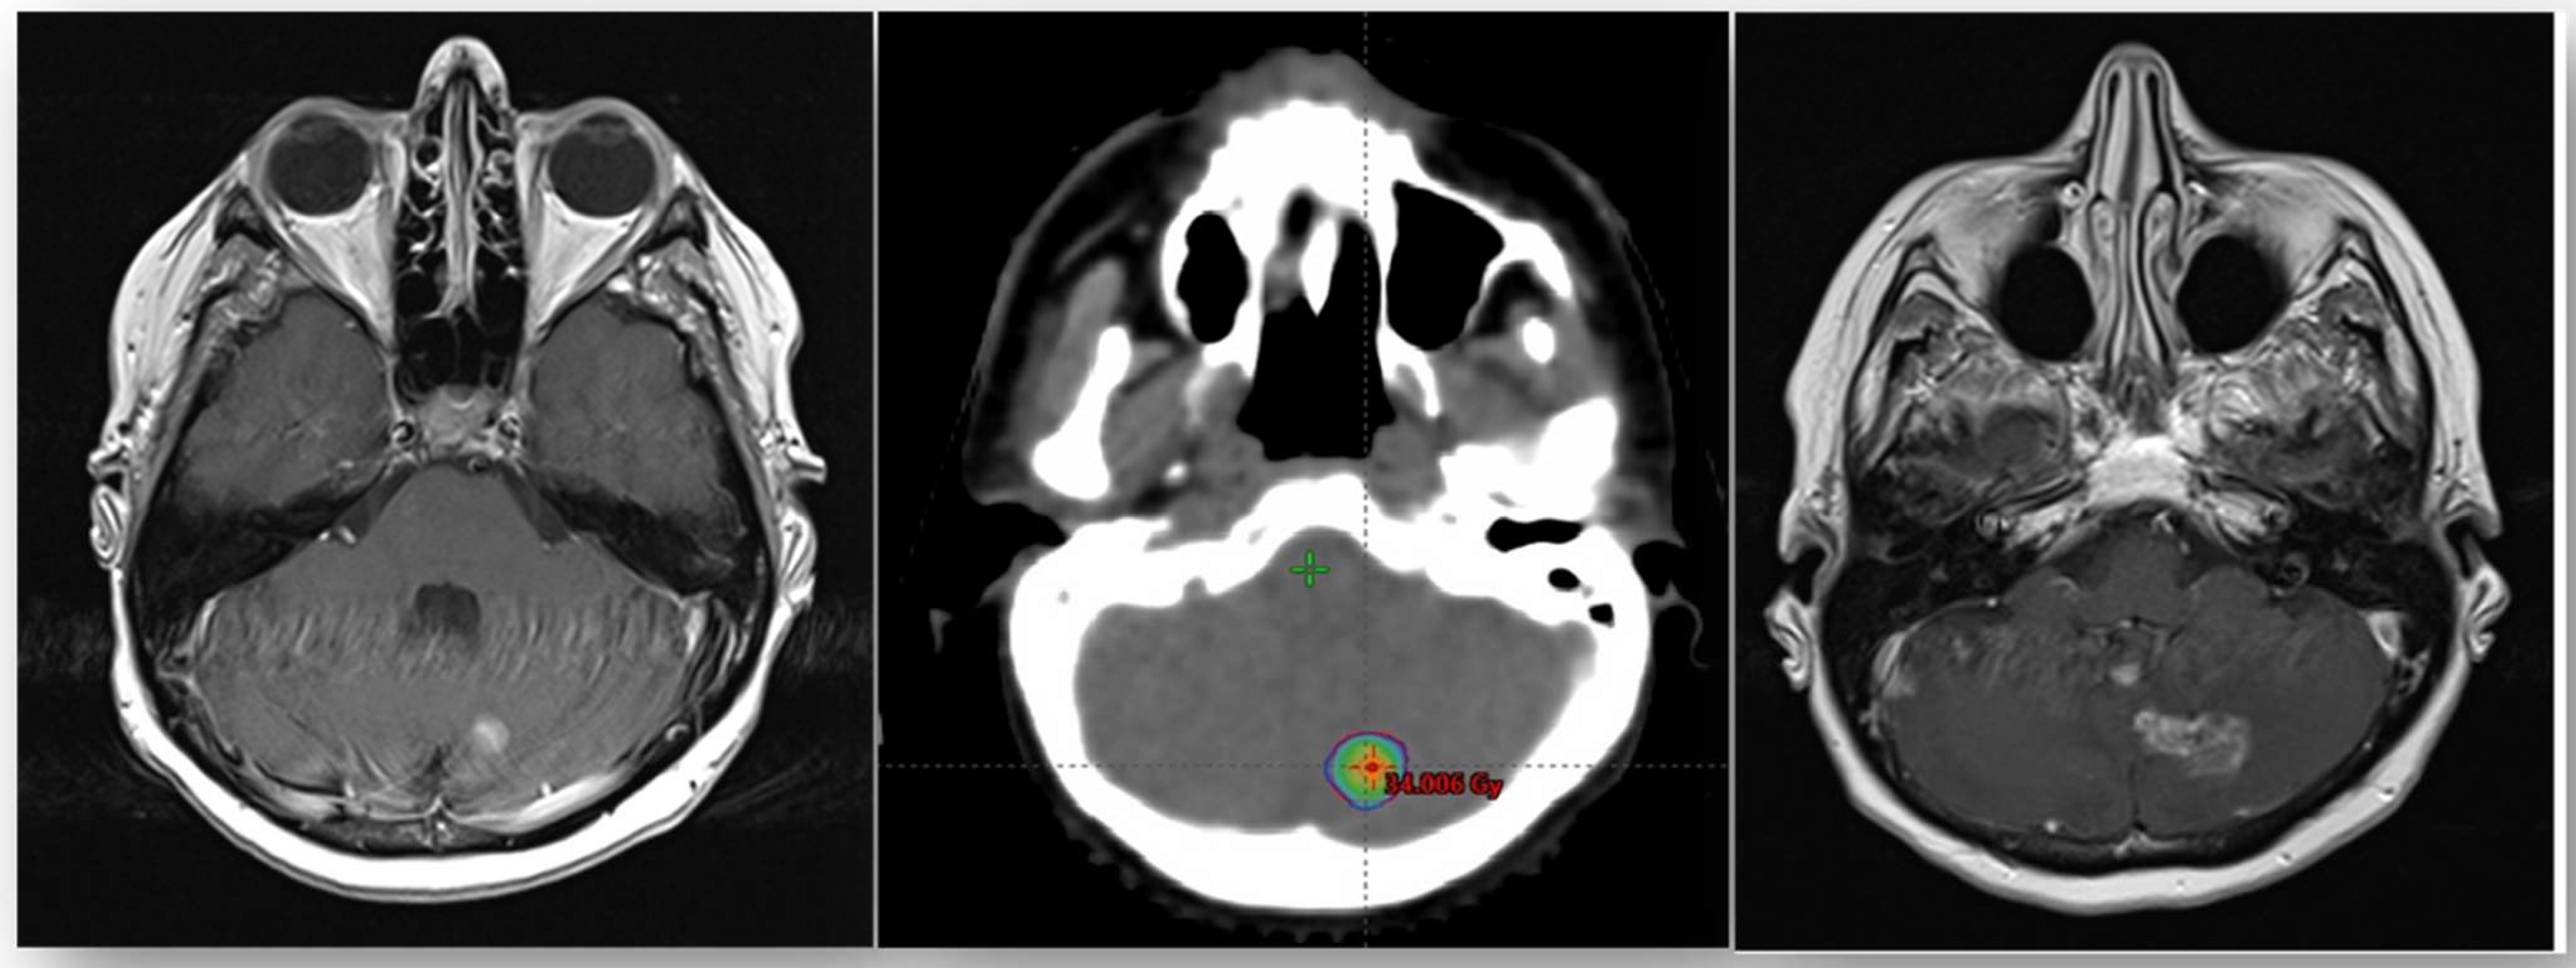

| Brain fSRT | 32 | 100 |

| PTV | ||

| Median | 2.26 cm3 | |

| Range | 0.8–54.4 | |

| Total dose | ||

| Median | 27 | - |

| Range | 12–27 | |

| Dose per fraction | ||

| Median | 9 | |

| Range | 4–9 | |